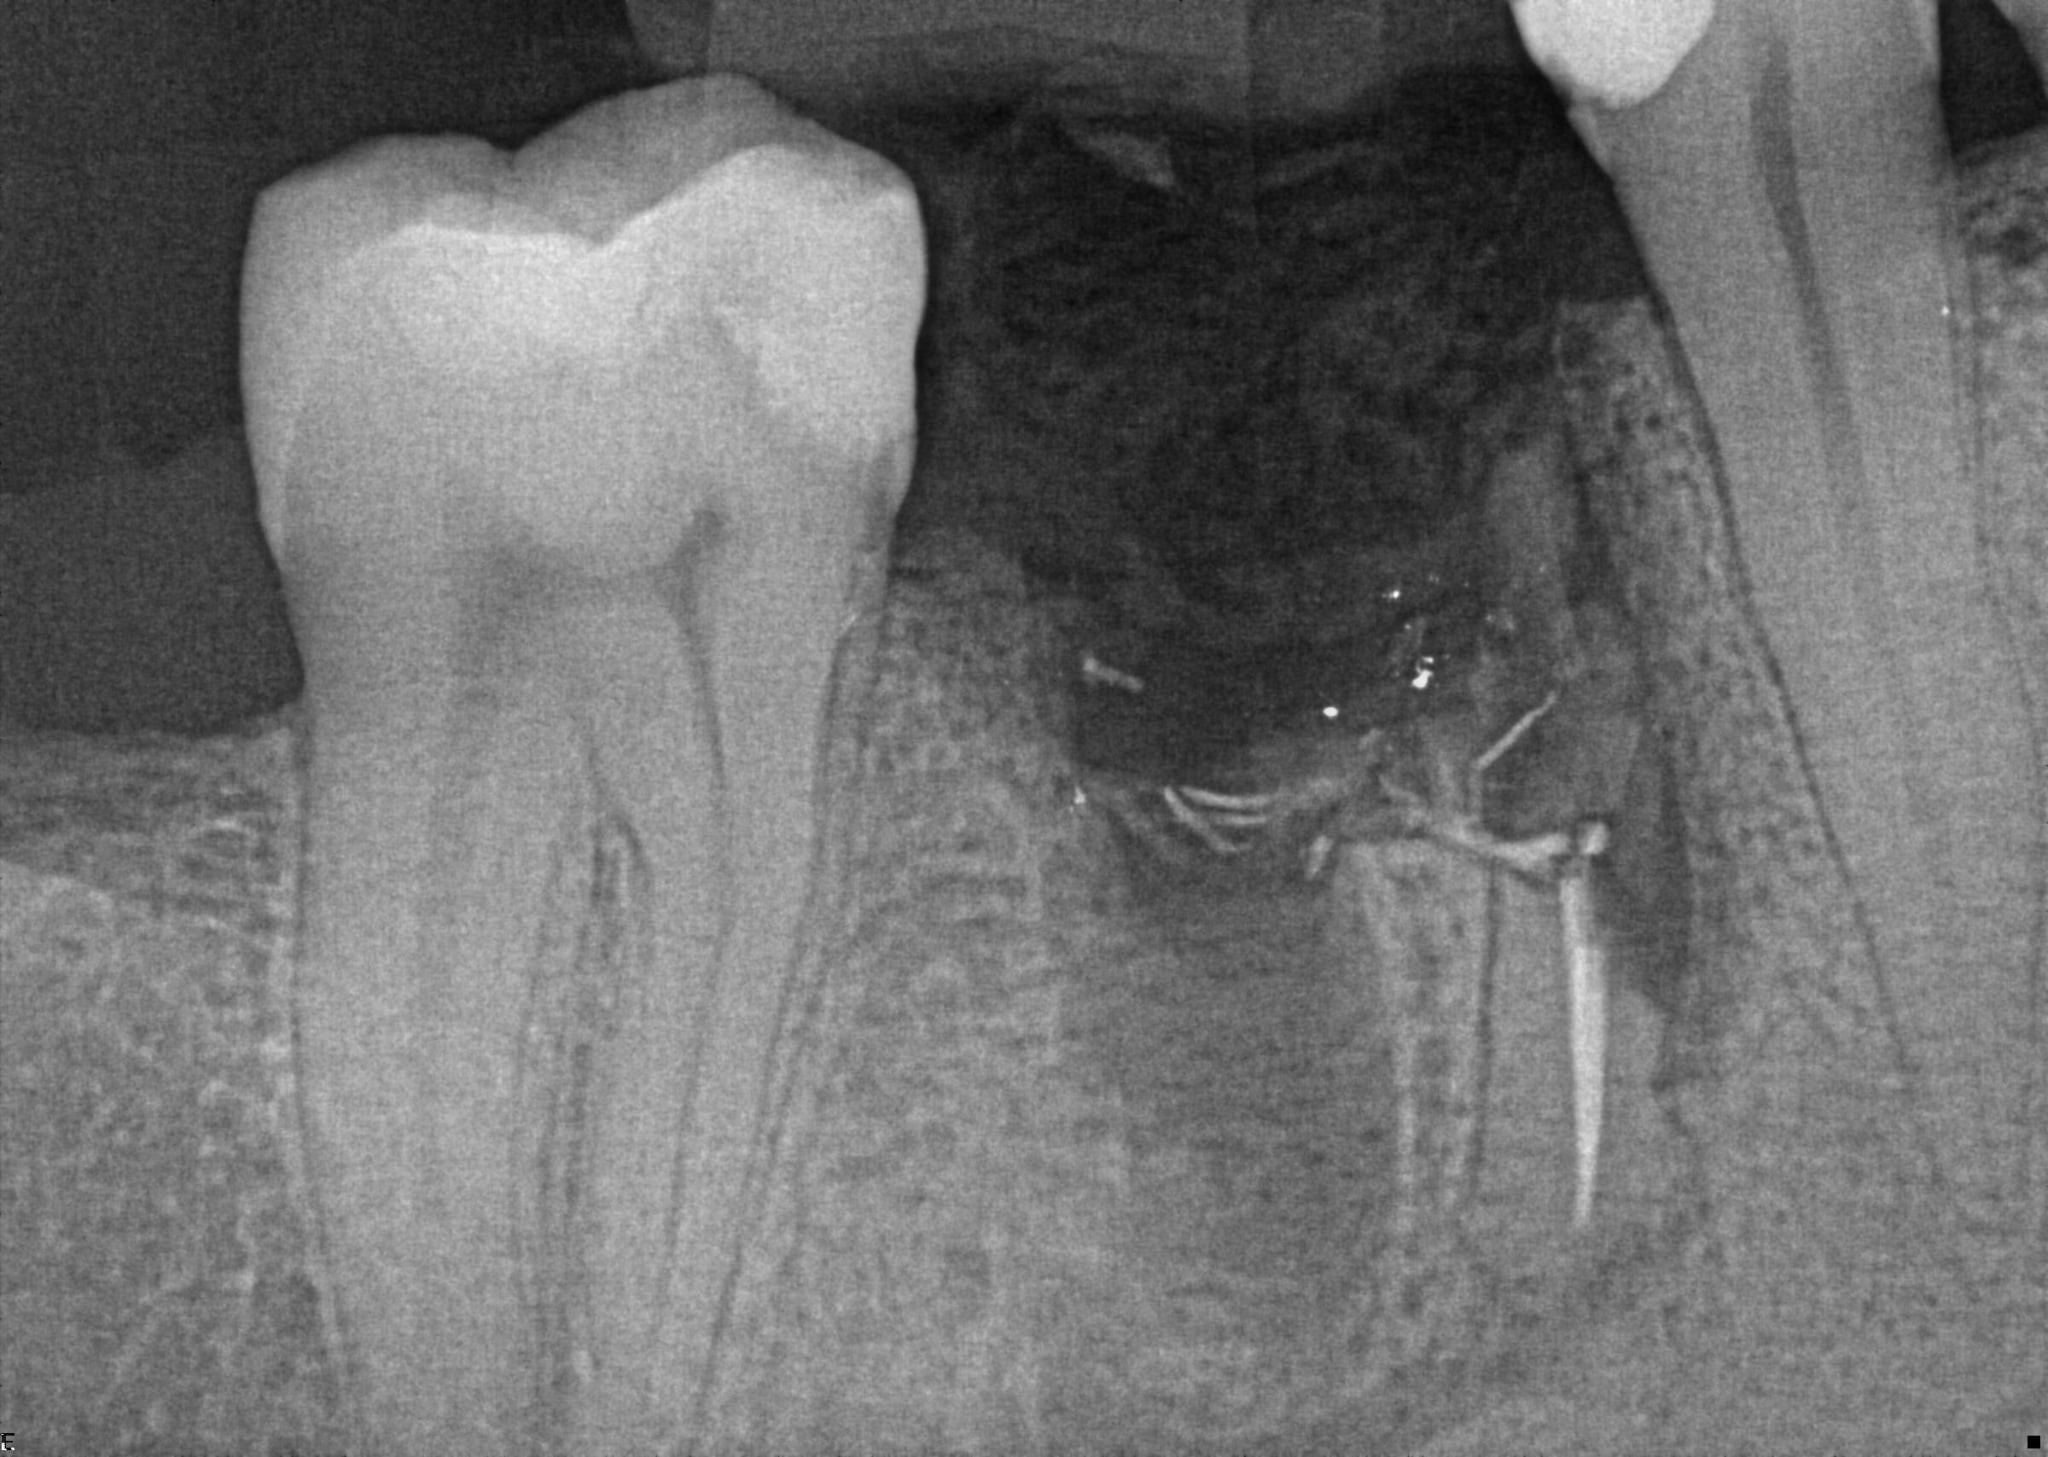

17. (Select ONE or MORE correct answer)

Regarding tooth 4.6, there is evidence of